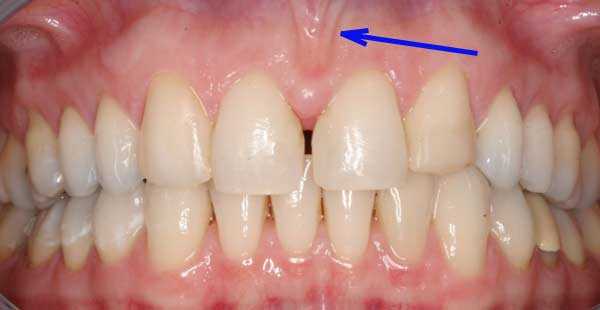

Пластика уздечки верхней губы у детейЧтобы ее увидеть, следует слегка приподнять верхнюю губу. Уздечка напоминает маленький треугольник, соединенный с десной около резцов.

Диагностировать проблему очень просто, нужно лишь приподнять губу, оценить положение полости. Если слизистая складка начинается в середине губы , на 4-6 мм выше десны, ее можно назвать слишком короткой. Такая уздечка может стать причиной развития патологий.

- Диастема, или щель между передними зубами. Дело даже не в заметном дефекте. Уздечка между зубами препятствует правильному положению зубов, из-за чего они травмируются и разъезжаются.

Нормальной считается уздечка, которая вплетается в десну на 0,5-1 см от основания передних резцов. Более низкое ее расположение приводит к тому, что уздечка может заходить за передние резцы, а место ее крепления с десной вообще не просматривается. То есть уздечка начинается в середине верхней губы и крепиться примерно на 0,4-0,6 см выше десны, обосновываясь в щели между передними резцами.

Короткую уздечку очень легко увидеть при визуальном осмотре. Для этого верхнюю или нижнюю губу отводят в сторону и рассматривают. При нормальном расположении она не влияет на прикус и не мешает разговаривать. Низкое же ее расположение может привести к множественным нарушениям не только речи, но и эстетики лица. Чтобы не допустить дефектов губы и речи ребенка, проводят операцию по пластике уздечки.